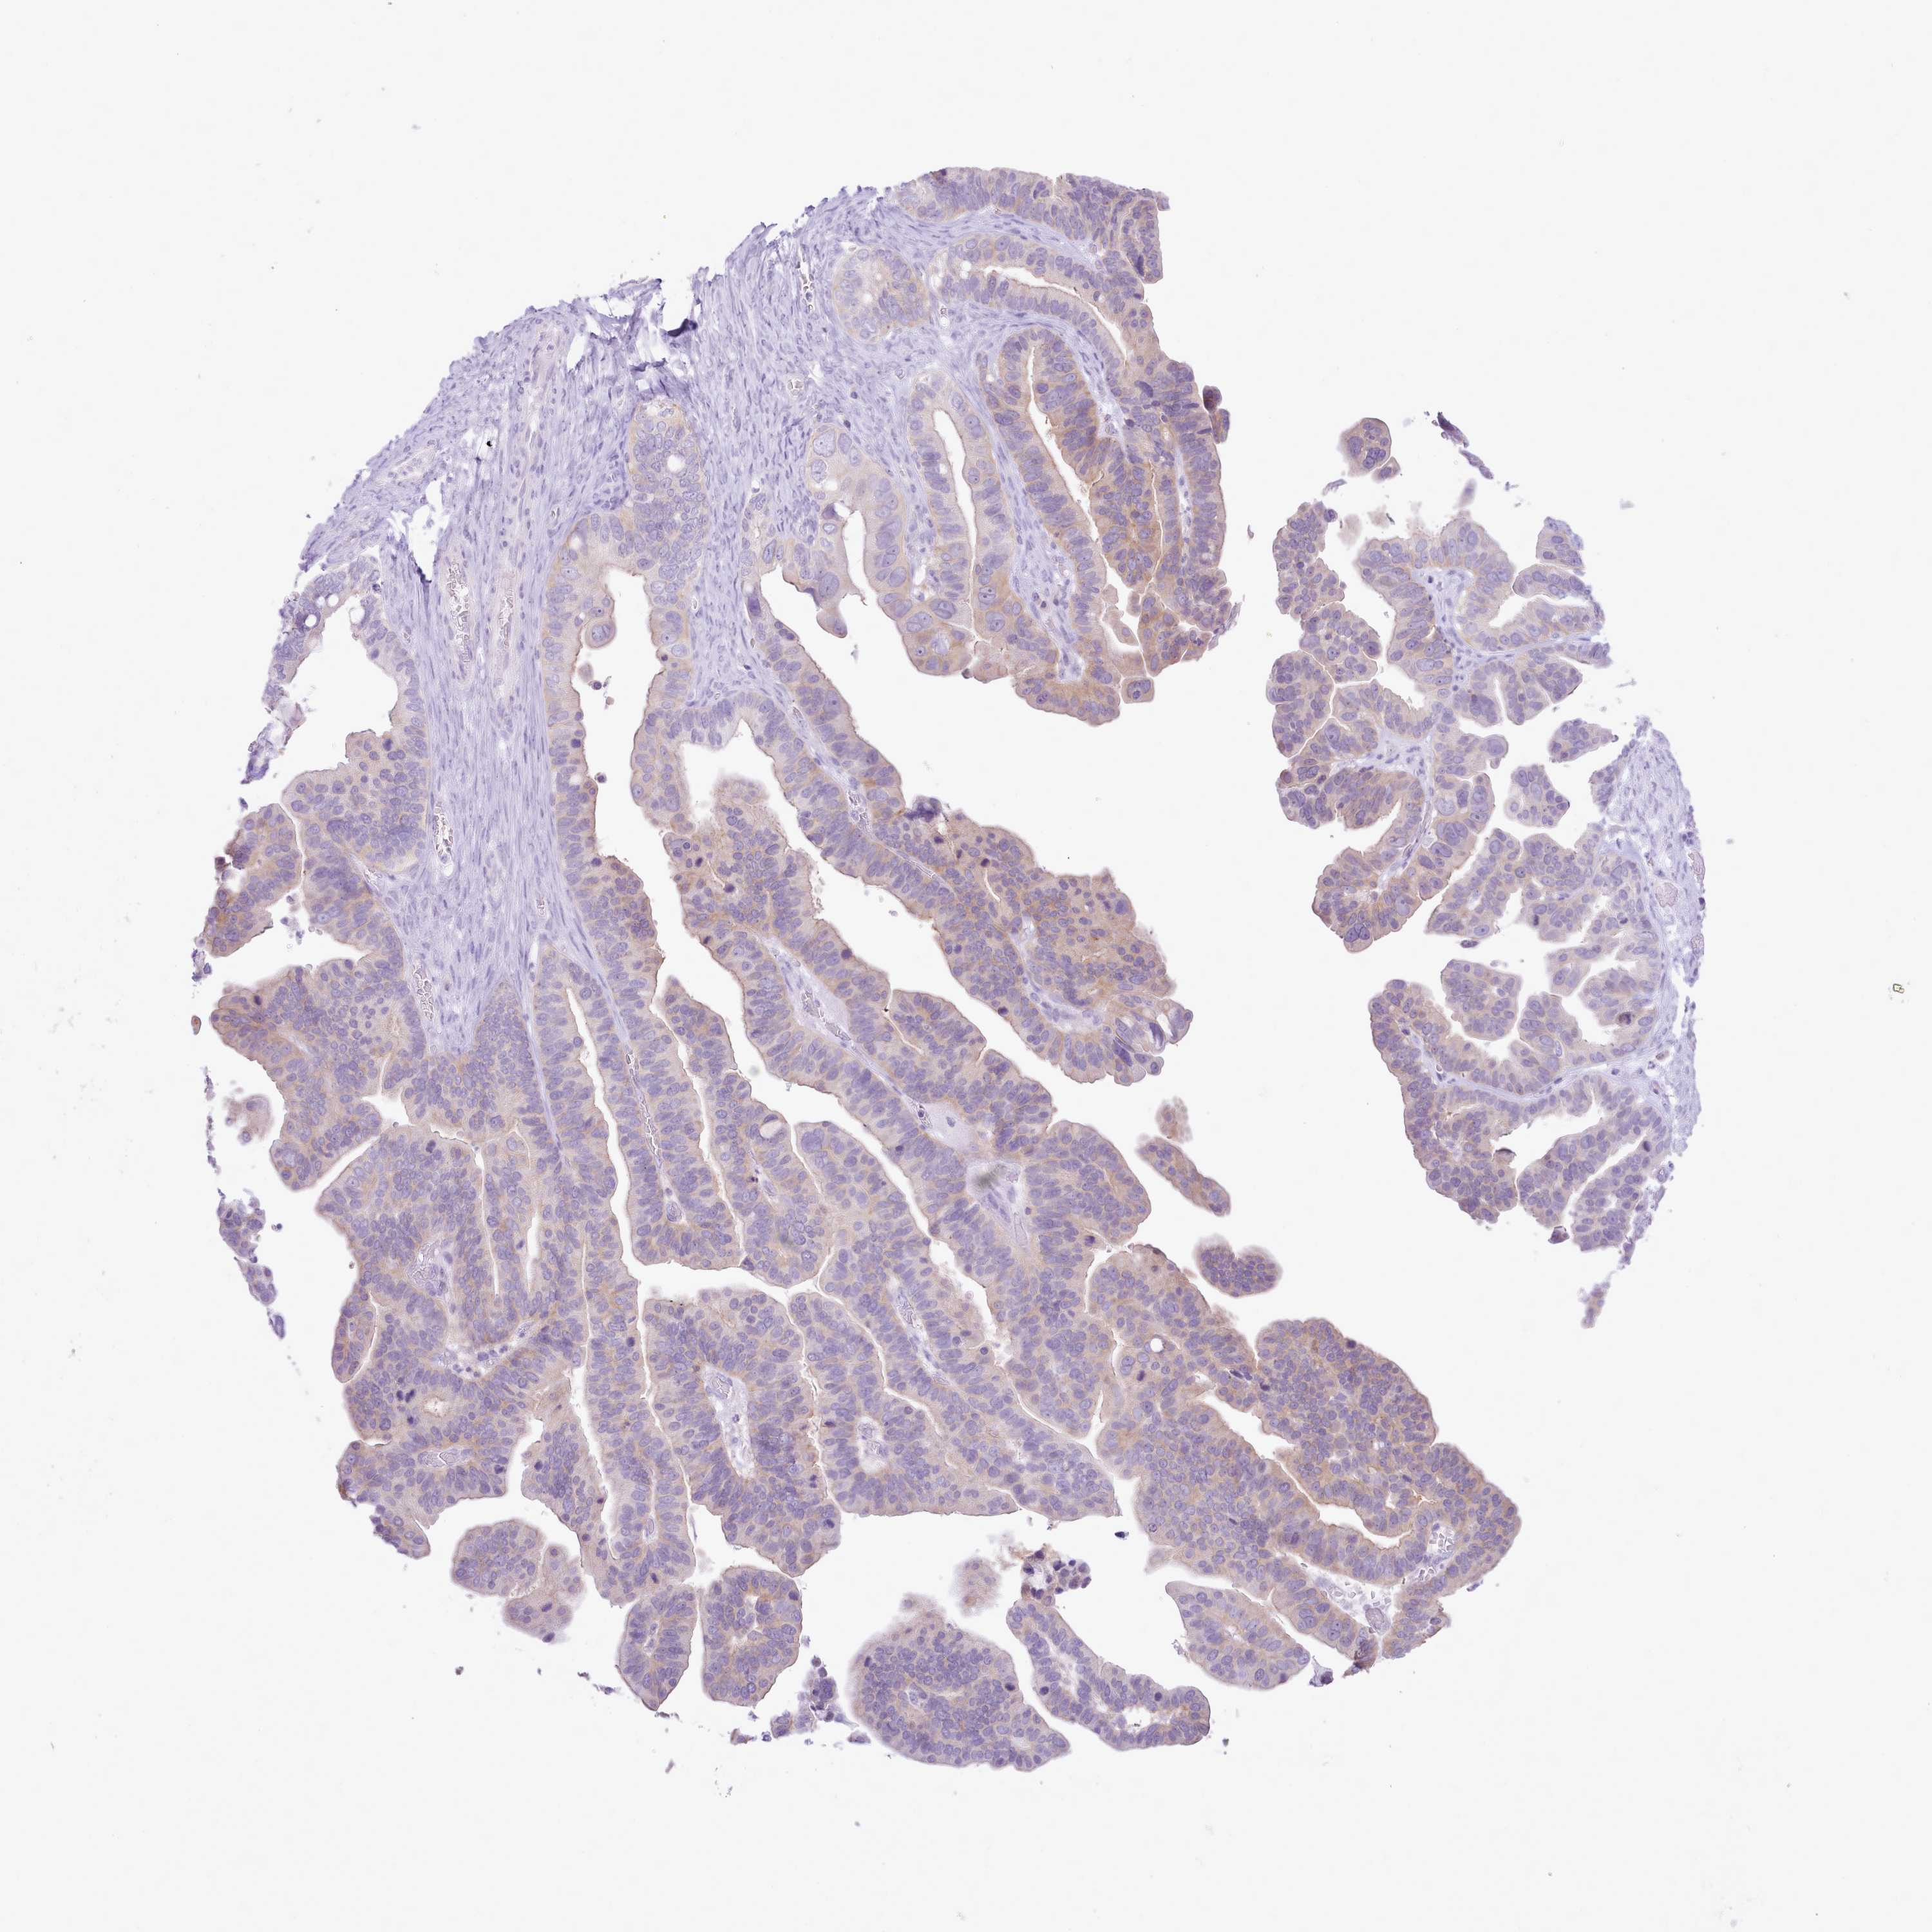

OVARIAN CANCER - Protein expressioni

A mouse-over function shows sample information and annotation data. Click on an image to view it in a full screen mode. Samples can be filtered based on level of antibody staining by selecting one or several of the following categories: high, medium, low and not detected. The assay and annotation is described here.

Note that samples used for immunohistochemistry by the Human Protein Atlas do not correspond to samples in the TCGA dataset.

Antibody stainingi

Antibody staining in the annotated cell types in the current human tissue is reported as not detected, low, medium, or high, based on conventional immunohistochemistry profiling in selected tissues. This score is based on the combination of the staining intensity and fraction of stained cells.

Each image is clickable and will lead to virtual microscopy that enables deeper exploration of all samples and also displays staining intensity scores, fraction scores and subcellular localization as well as patient and tissue information for each sample.

Antibody HPA049973

Staining

High

Medium

Low

Not detected

Intensity

Strong

Moderate

Weak

Negative

Quantity

>75%

75%-25%

<25%

None

Location

Nuclear

Cytoplasmic/membranous

Cytoplasmic/membranous,nuclear

Cystadenocarcinoma, serous, NOS

Carcinoma, NOS

Cystadenocarcinoma, mucinous, NOS

Carcinoma, endometroid